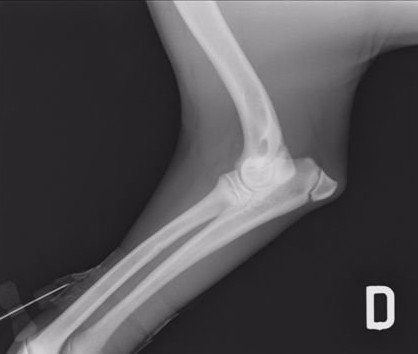

Displasia del gomito e neurologia veterinaria

Oltre all’anca, la nostra clinica si occupa anche della displasia del gomito, una patologia multifattoriale che colpisce spesso le razze di taglia grande. Essa può derivare da:

- frammentazione del processo coronoideo (FCP);

- mancata unione del processo anconeo (UAP);

- osteocondrite dissecante (OCD);

- incongruenza articolare (INC).